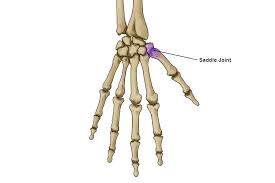

What is a Saddle Joints?

What are Saddle Joints?

A saddle joint is a type of biaxial and movable joint that allows movements on two planes–flexion or extension and abduction or adduction. This joint is mainly formed between the bones, whose articulating surfaces have both concave and convex regions.

Saddle joints are also known as sellar joints, which are highly flexible joints. There are only a few saddle joints present in our body. These include joints at the base of the thumb finger, upper part of the breastbone and the incudomalleolar joint, which is located in the inner human ear.

Features of Saddle Joints

- Saddle joints are similar to condyloid joints.

- The name saddle joint is mainly derived from its shape or structure.

- This joint looks quite similar to the saddle seat, hence named saddle joint.

- The connecting bones are shaped like interlocking saddles.

- This joint allows a greater range of motion than other joints.

- Compared to ball and socket joints, saddle joints do not provide a complete rotation.

- Flexibility and the interlocking is more in saddle joints when compared to other types of synovial joints.

- The structure of saddle joints is a combination of both hinge joint and ball and socket joint.